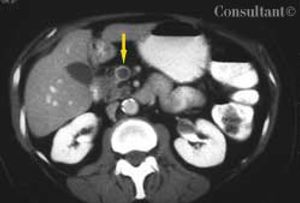

A 65-year-old woman with metastatic adenocarcinoma of the colon was undergoing chemotherapy following a colectomy and a hepatic wedge resection. The physical examination and laboratory data were unremarkable.